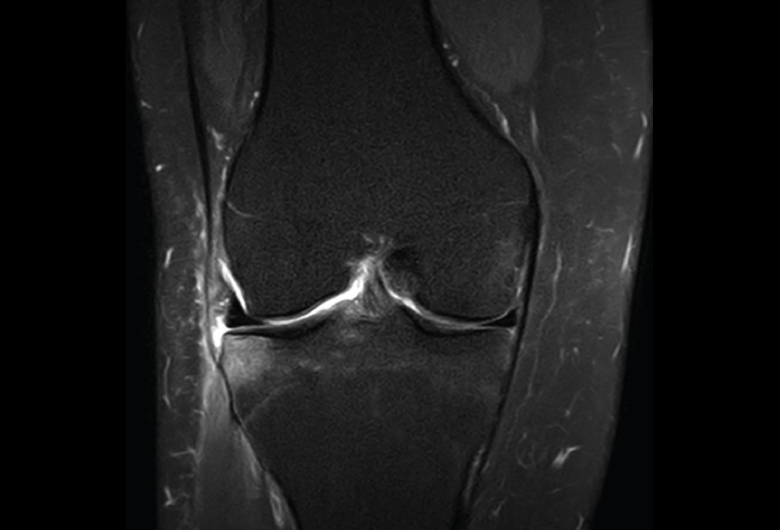

1.2. Ligamentos

Se visualizan como estructuras lineales hipointensas en todas las secuencias.

1.2.1. Ligamentos laterales

Figura 36. Corte de secuencia coronal T2 Fat-Sat: ligamentos colaterales normales.

Ligamento lateral interno (LLI) y ligamento lateral externo (LLE) (Figuras 36, 37, 38 y 39).

Figura 37. Corte de secuencia coronal T2 Fat-Sat de rodilla: pequeño edema en el LLI, banda medial por esguince del LLI de grado I.

Figura 38. Corte de secuencia coronal T2 Fat-Sat de resonancia magnética de rodilla: edema y pequeña rotura de fibras mediales del ligamento lateral interno (LLI). Esguince del LLI de grado II.

Figura 39. Corte de secuencia coronal T2 Fat-Sat de resonancia magnética de rodilla: edema y rotura del ligamento lateral externo de su inserción peroneal con retracción ligamentosa. Esguince de grado III.